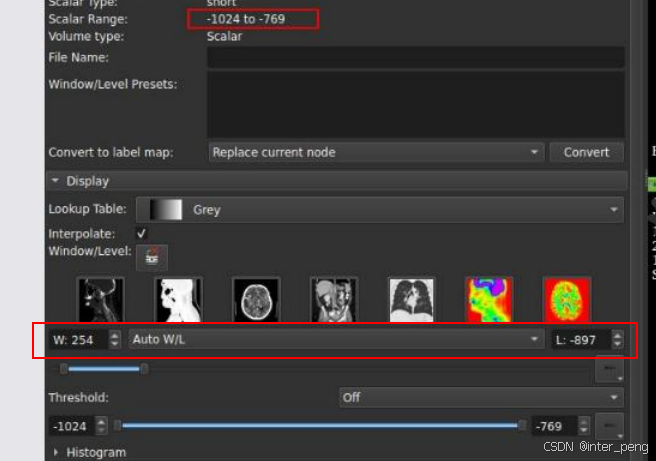

切换到Volumes模块后,可以看到这个序列影像,它的Scalar Range的范围是: -1024 ~ -769.

这里的Scalar Range, 其实就是CT值。

其实,之所以这个有问题的序列,在我们的软件产品中黑屏,而在slicer, 或其他的一些dicom viewer里面能够正常展示。是因为,这些软件,它们会根据这个序列的灰度范围,而自动调节显示时使用的窗宽窗位。而我们的软件,由于是给特定部位使用的,所以里面有一个默认的窗宽窗位,就像第一幅图中展示的, ww = 150, wl = 90.

而slicer在加载这个序列后,它的窗宽窗位,会自适应地调整成为: ww = 254, wl = -897.